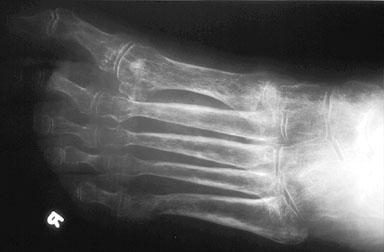

una disminución de la densidad de la masa ósea y es difícil de diagnosticar anticipadamente, ya que no

posee síntomas visibles. Una primera evidencia de la aparición de

esta enfermedad suelen ser fracturas de muñeca, cadera, o columna.